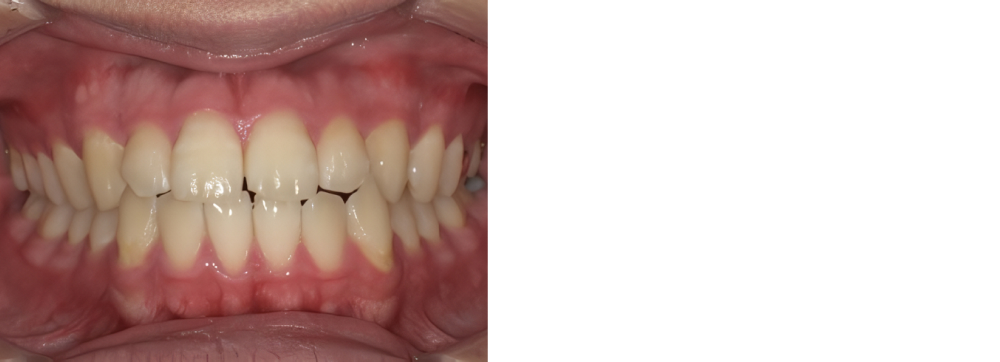

成人矯正

術前

術後

| 治療内容 | 掲載準備中 |

|---|---|

| 治療期間・回数 | 掲載準備中 |

| 費用 ※自由診療となります |

掲載準備中 |

| リスク・副作用 |

|